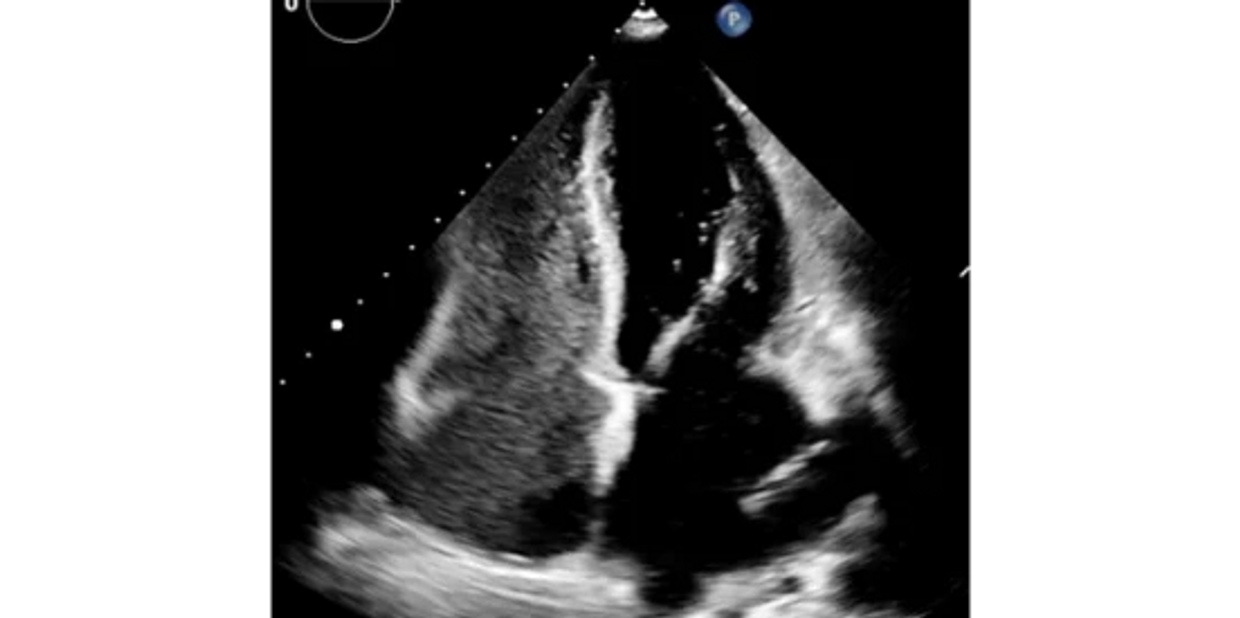

Ecocardiograma contrastado

• El ecocardiograma transtorácico contrastado (o "estudio de burbujas") consiste en realizar un ultrasonido del corazón y administrar un poco de solución salina a través de una vía intravenosa.

• Nos permite identificar algunos cortocircuitos de la circulación (intracardiacos o extracardiacos), lo cual es importante para la evaluación de diversas enfermedades.